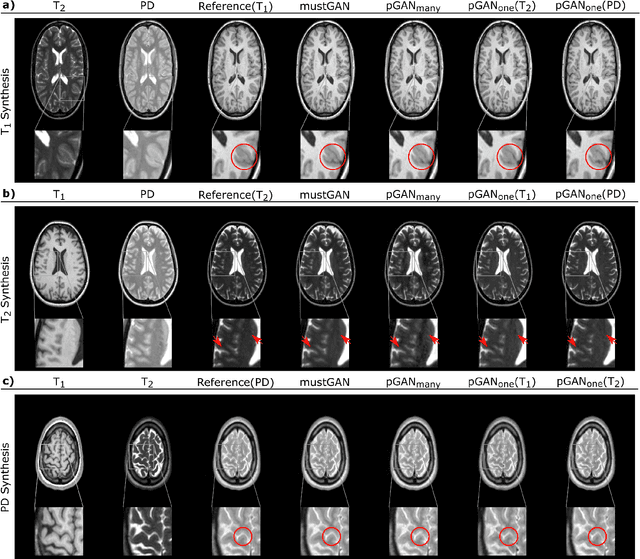

Abstract:Multi-modal imaging is a key healthcare technology in the diagnosis and management of disease, but it is often underutilized due to costs associated with multiple separate scans. This limitation yields the need for synthesis of unacquired modalities from the subset of available modalities. In recent years, generative adversarial network (GAN) models with superior depiction of structural details have been established as state-of-the-art in numerous medical image synthesis tasks. However, GANs are characteristically based on convolutional neural network (CNN) backbones that perform local processing with compact filters. This inductive bias, in turn, compromises learning of long-range spatial dependencies. While attention maps incorporated in GANs can multiplicatively modulate CNN features to emphasize critical image regions, their capture of global context is mostly implicit. Here, we propose a novel generative adversarial approach for medical image synthesis, ResViT, to combine local precision of convolution operators with contextual sensitivity of vision transformers. Based on an encoder-decoder architecture, ResViT employs a central bottleneck comprising novel aggregated residual transformer (ART) blocks that synergistically combine convolutional and transformer modules. Comprehensive demonstrations are performed for synthesizing missing sequences in multi-contrast MRI and CT images from MRI. Our results indicate the superiority of ResViT against competing methods in terms of qualitative observations and quantitative metrics.